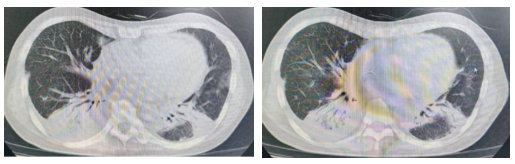

2024-07-10复查胸部CT:双肺多发结节、类结节,双肺散在炎症及纤维化灶,炎症较前增多,双肺下叶及左肺舌段部分实变,内可见支气管空气征,双肺弥漫性支气管树芽征改变(图3),继续L-AmB 150mg/天(静脉)抗真菌治疗,抗细菌感染采用降阶梯治疗方案

图3. 2024-07-10 胸部HRCT影像